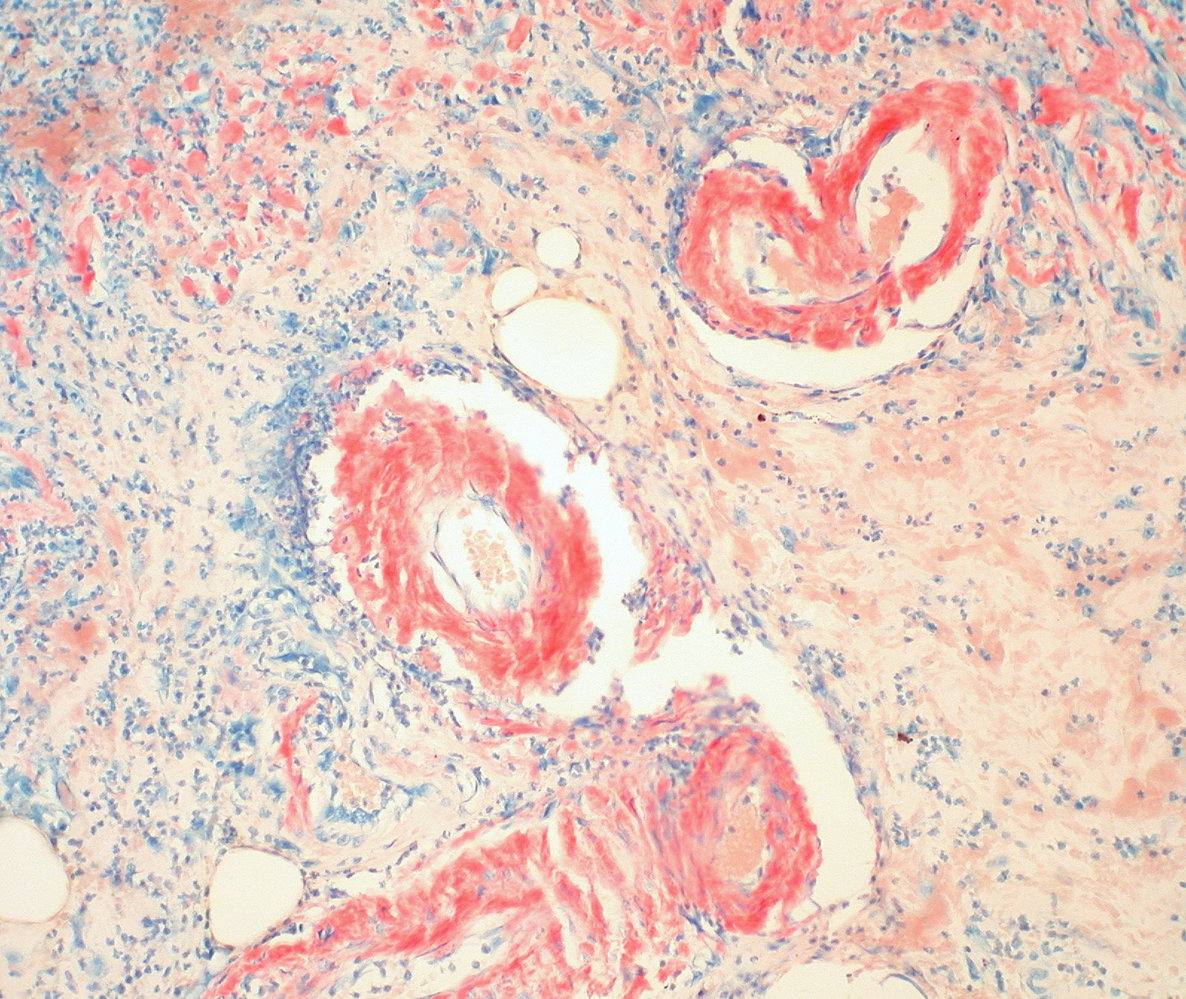

• Kidney tissue biopsy; findings include: [15]

• Global and segmental amyloid deposition

• Diffuse and/or focal glomerular involvement

• Enlargement of glomeruli

• Tubular atrophy

• Interstitial fibrosis